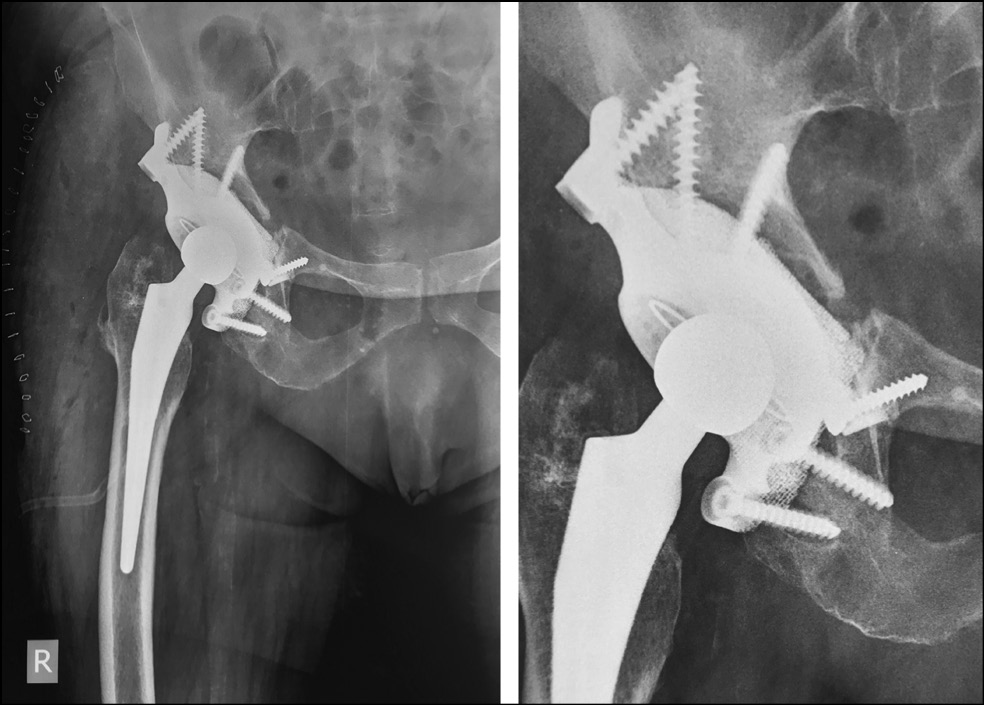

A 69-year-old patient underwent primary total hip replacement of the right hip joint with a Biomet endoprosthesis for right-sided coxarthrosis in 2010. In 2011, a similar operation using a Zimmer endoprosthesis was performed for left-sided coxarthrosis. In 2012, pain in the right hip joint region appeared and began to progress. In 2013, a revision hip replacement of the right hip joint was performed for acetabular component instability. Postoperatively, the patient noted repeated dislocations of the head of the right hip joint endoprosthesis with subsequent closed repositioning. In 2015, a revision hip replacement with a Burkh–Schneider antiprotrusion ring was performed for recurrent dislocations of the head of the right hip joint. Eighteen months after surgery, pain in the operated joint recurred. In November 2017, the patient was admitted to the endoprosthesis department of the N.N. Priorov National Medical Research Center of Traumatology and Orthopedics. The assessment of the right hip joint function according to the Harris hip scale (HHS) was 18 points, the severity of pain syndrome according to the visual analog scale (VAS) was 74 points (for a more accurate assessment, the scale was measured in millimeters), and the patient’s social adaptation according to the Western Ontario and McMaster Universities Osteoarthritis Index (WOMAC) scale was 92 points. Radiographs of the pelvic bones in a straight projection were obtained (Fig. 1).

Fig. 1. Preoperative radiograph of a 69-year-old patient: type IIIB acetabular defect according to W.G. Paprosky.

For a more detailed visualization of the defect of the bones forming the acetabulum, multispiral computed tomography (CT) with 3D reconstruction was performed (Fig. 2).